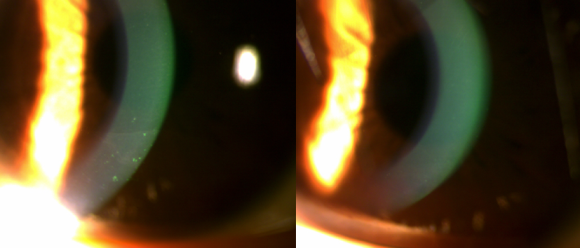

세극등현미경으로 자세히 살펴보니 좌안 아랫쪽 각막에 변화가 있었습니다.

더구나 각막에 아주 작은 점 모양의 손상이 여러 군데 생긴 점상각막염까지 동반된 상태였습니다.

수술 후 나비넥타이 모양의 난시가 사라지고

매끄럽고 넓은 광학부가 형성된 것을 볼 수 있고,